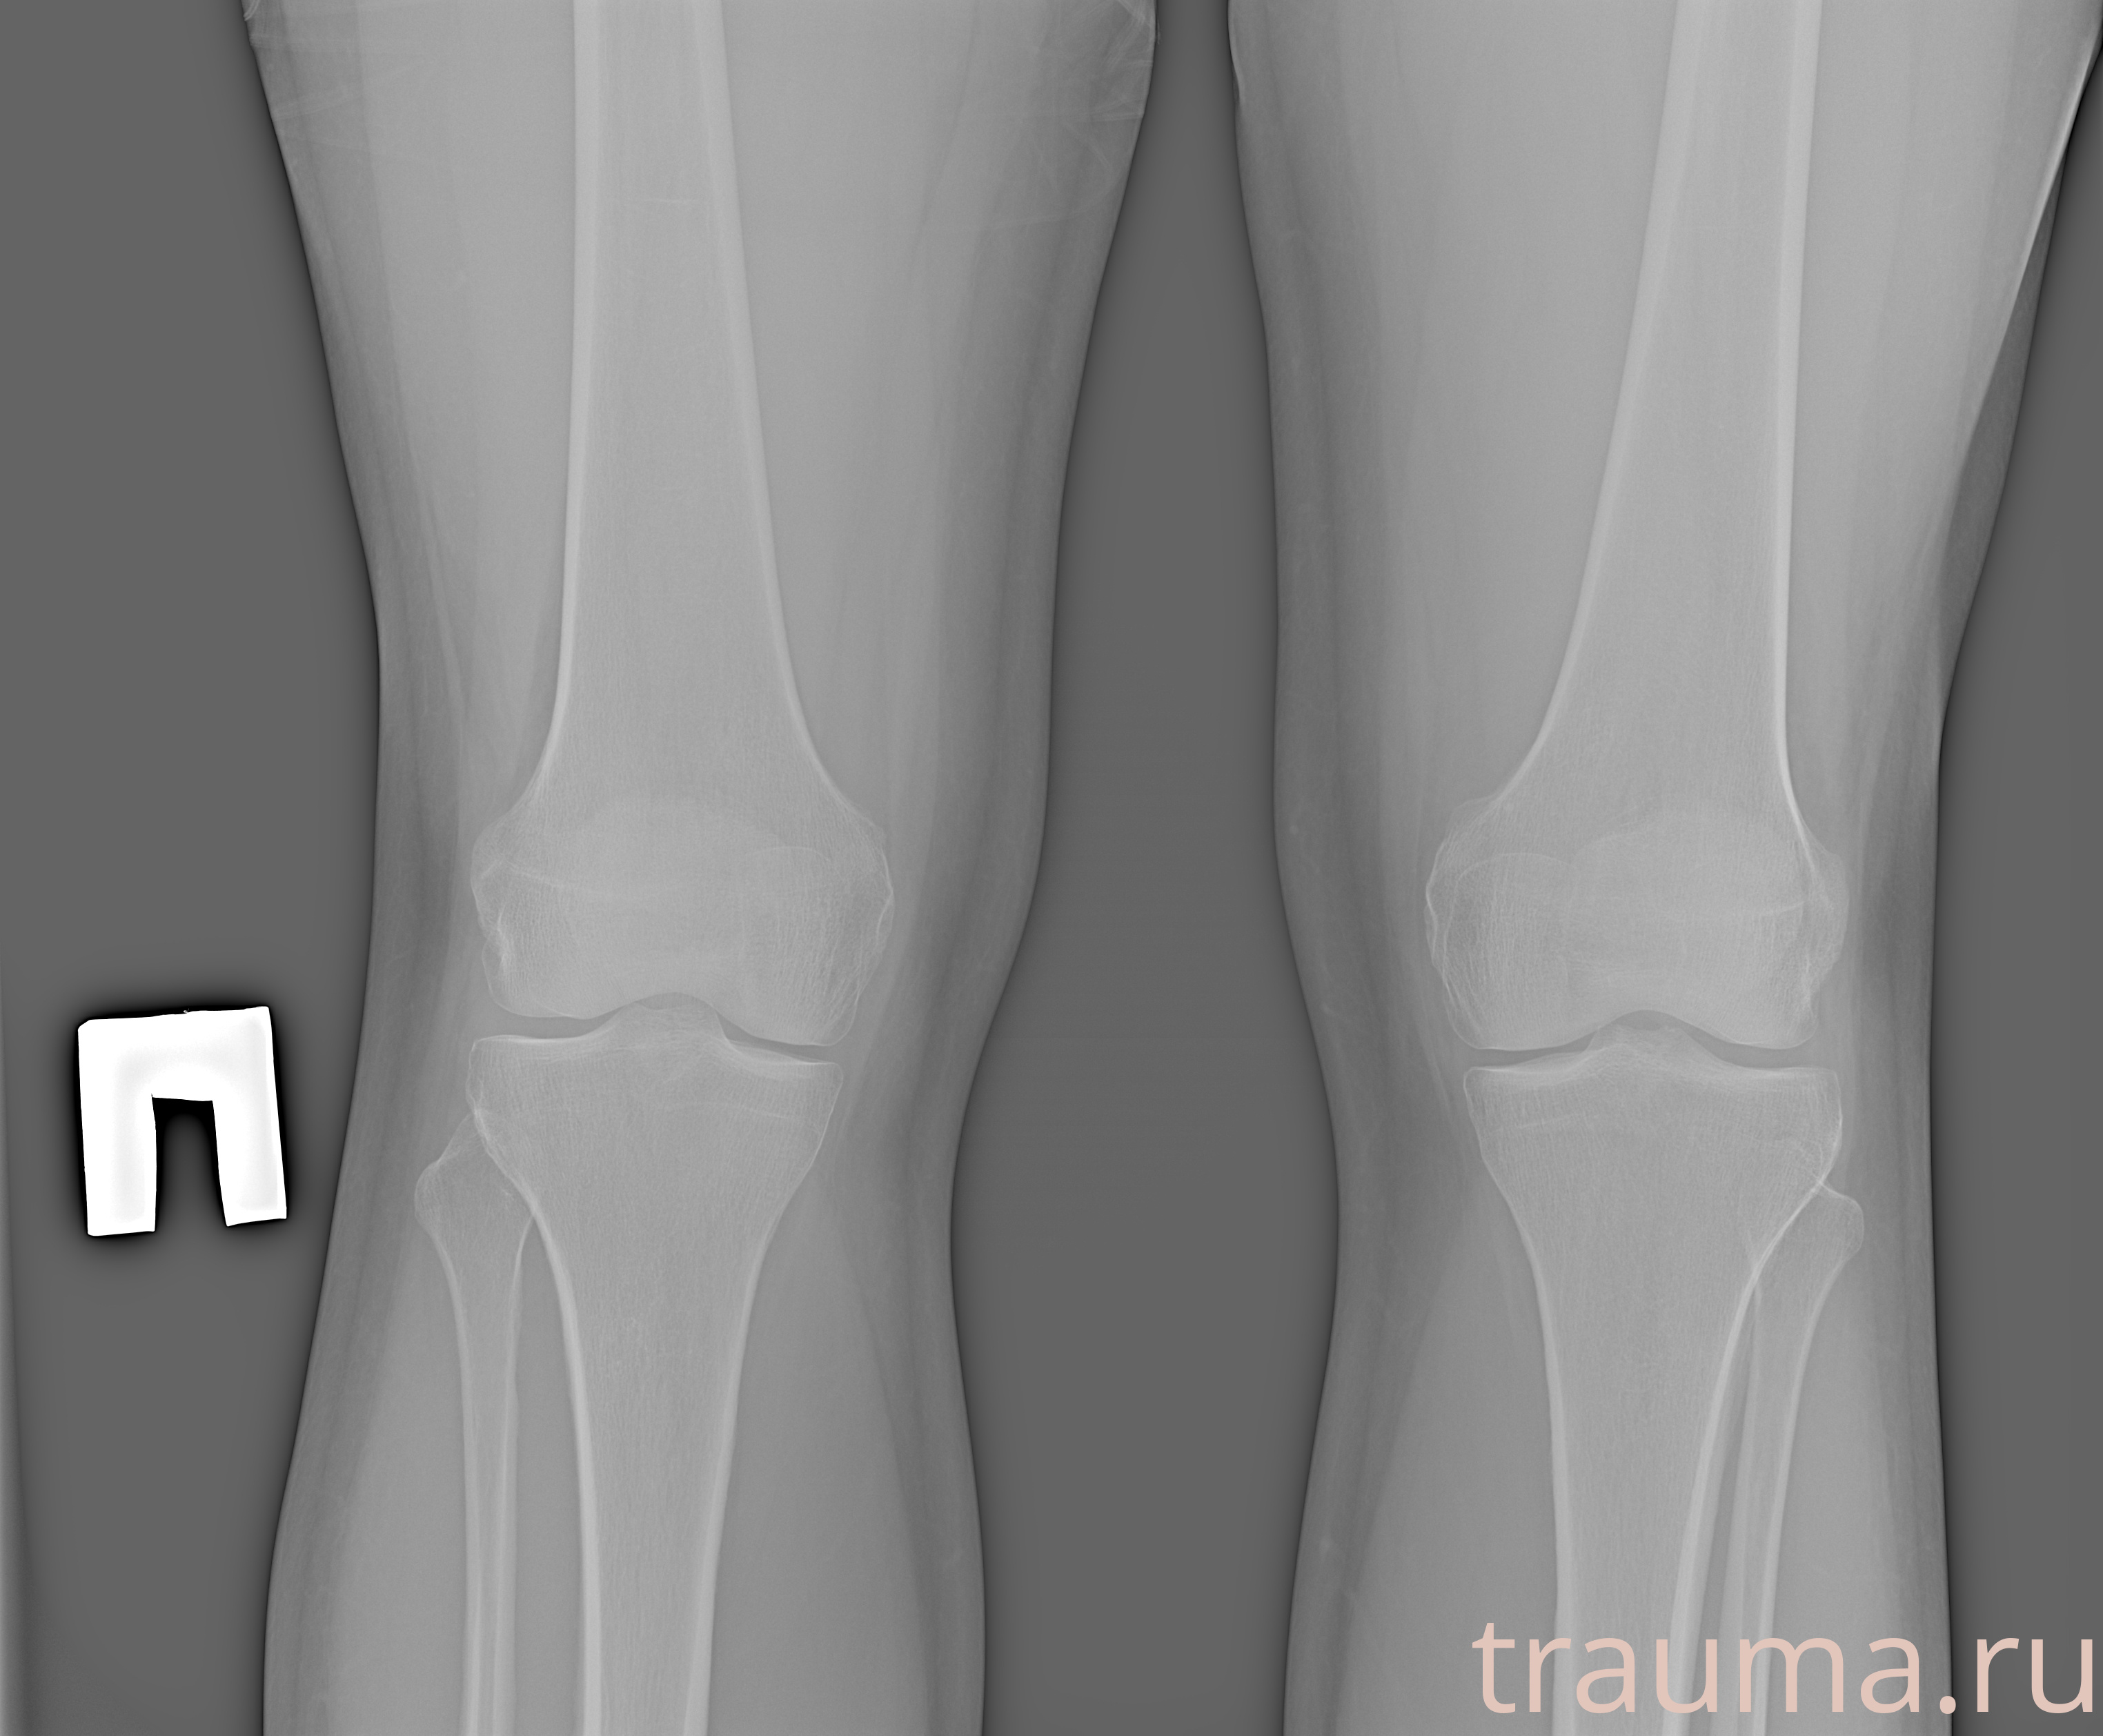

Рентгенограммы